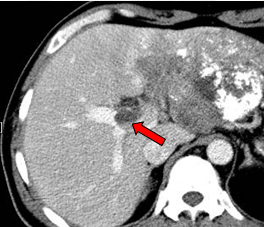

肝左叶巨块型肝癌(13.8cm×9.1cm),伴肝右后叶子灶,门静脉左支、肝左静脉及下腔静脉内癌栓。

2011-02-12复查CT示:肝左叶碘油散在沉积,病灶大部分仍有活性,肝右后叶病灶未见碘油沉积;门静脉癌栓较前进展,累及主干及右支;肝左静脉及下腔静脉内癌栓无明显变化。AFP:26802 ng/ml。

2011-04-20复查CT示:肝左叶病灶较前缩小,肝右叶病灶见碘油致密沉积;门脉癌栓左支较前缩小,右支癌栓消失;下腔静脉、肝左静脉癌栓消失。AFP:4983 ng/ml。

2011-06-09(第二次TACE后4个月)复查肝脏CT示:肝左叶病灶继续缩小,但仍有肿瘤残留。AFP:8137 ng/ml(较上次复查明显升高)。

2011-08-15复查CT示:肝左叶病灶大小较前相仿,仍有肿瘤残留。